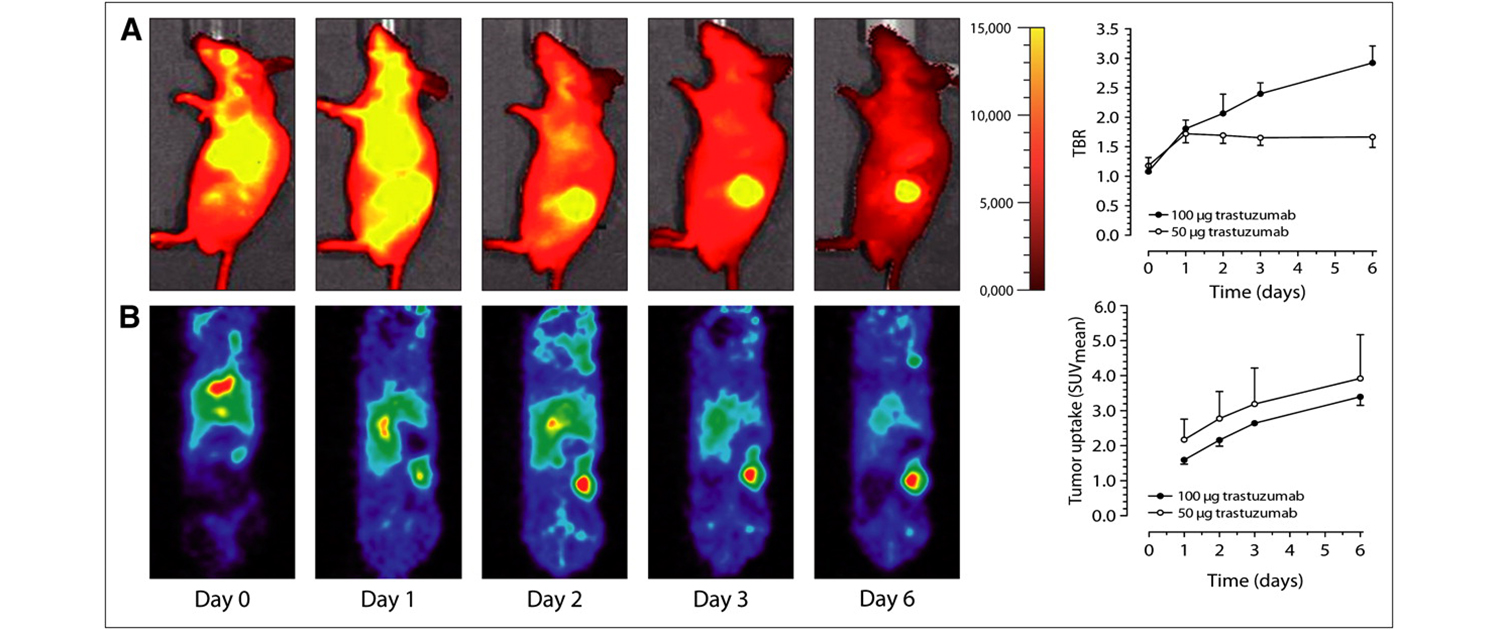

Image analysis is a critical component of clinical and preclinical imaging research, providing a means of quantifying and interpreting the data generated by imaging modalities such as PET, SPECT, and CT. In clinical imaging, image analysis is used to aid in diagnosis and treatment planning. For example, in oncology, image analysis can be used to assess the response to chemotherapy and radiation therapy, providing a means of monitoring the effectiveness of treatment and making adjustments as necessary.

In cardiology, image analysis can be used to evaluate blood flow and cardiac function, enabling the diagnosis and treatment of heart disease. In preclinical imaging research, image analysis plays a crucial role in the development of new treatments and therapies. Image analysis algorithms can be used to quantify the effects of drug treatments or surgical procedures on biological processes such as blood flow and metabolic activity. By providing a means of objectively assessing treatment efficacy, image analysis helps to optimize treatment protocols and improve patient outcomes.

The same image analysis techniques can be applied to both clinical and preclinical images, allowing for a seamless transition between research modalities. Moreover, image analysis has additional applications in clinical research, beyond the evaluation of disease progression or response to therapy. For example, image analysis can be used for radiation treatment planning to optimize the radiation dose and minimize side effects.

Image analysis can also be used to evaluate the efficacy of medical devices or surgical procedures. Additionally, image analysis can be used in radiomics, which involves the high-throughput extraction of large amounts of data from medical images, allowing for the identification of imaging biomarkers that can help in patient diagnosis and prognosis. Overall, image analysis is a powerful tool in both preclinical and clinical research, with a wide range of applications beyond disease evaluation.

At our company, we provide a wide range of image analysis services for both preclinical and clinical imaging research. Our team of experts has extensive experience in conducting image analysis for various modalities, including PET, SPECT, CT, and optical imaging. We offer a comprehensive set of services, such as image registration, segmentation, quantification, and statistical analysis. We understand the importance of accurate and precise image analysis in the success of research projects, and we use state-of-the-art software and techniques to deliver reliable and reproducible results.